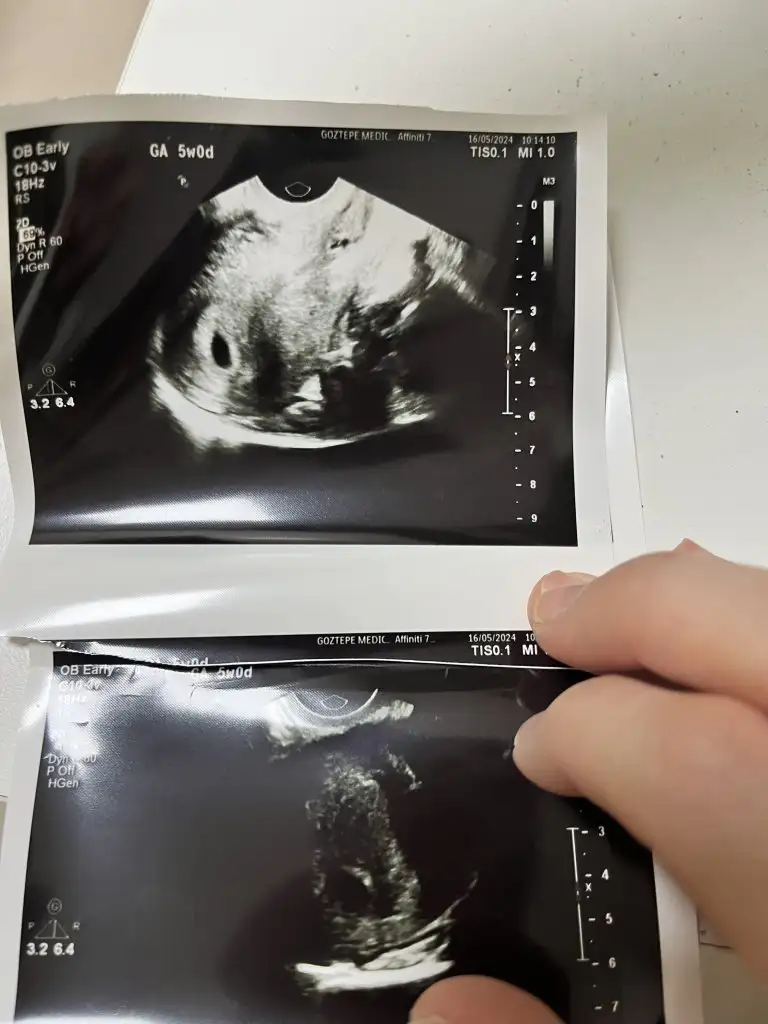

Kızlar selam, ben de dün doktora gittim, sata göre 5+6 görünüyordu ama doktor tam 5 haftalık dedi. Geç döllenme mi olmuş oluyor bu durumda? Görüntü de böyle. ♥️ umarım hepimiz için sağlıklı bir süreç ilerle ♥️

Eklentiler

• IMG_4593.webp

IMG_4593.webp

37,3 KB · Görüntüleme: 98